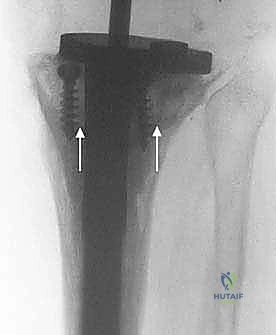

4. المخاريط والأكمام المعدنية المسامية (Porous Metaphyseal Cones & Sleeves)

هذه هي أحدث الثورات في عالم جراحة مراجعة المفاصل، وهي التقنية المفضلة لدى الأستاذ الدكتور محمد هطيف في حالات الفقدان العظمي الشديد (النوع الثاني والثالث من AORI). تُصنع هذه المخاريط من معادن عالية المسامية (مثل التنتالوم أو التيتانيوم المطبوع ثلاثي الأبعاد) التي تحاكي بنية العظم الإسفنجي.

تُزرع هذه المخاريط في التجاويف الكبيرة في قصبة الساق، وبفضل مساميتها العالية، ينمو عظم المريض الطبيعي داخل مسام المعدن (Osseointegration)، مما يوفر ثباتاً حيوياً وميكانيكياً هائلاً ومستداماً مدى الحياة.

بناءً على التقييم، يبدأ الجراح في تعويض العظم. إذا تم اختيار المخاريط المسامية (Cones)، يتم تحضير التجويف العظمي باستخدام مبشرة خاصة لتطابق شكل المخروط. يتم إدخال المخروط المعدني وتثبيته بقوة داخل العظم، ليصبح قاعدة صلبة ومستوية.